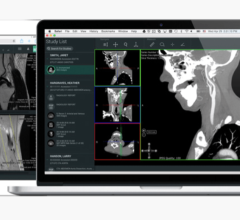

Confirma has spent years developing the extensive CAD algorithms, intellectual property and validation required of these highly technical clinical tools. The flagship product, CADstream, has over 1,200 systems implemented for breast and prostate MRI, and several additional solutions are in development. “Our customers understand the core benefits of CAD as a clinical workflow tool,” says Wayne Wager, CEO of Confirma. “By combining our patented CAD applications with Merge’s broader health IT solutions and global presence, we can better take advantage of current and future growth opportunities and, thus, extend our solutions to more clinicians.”